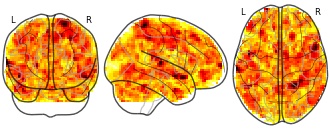

BrainPedia: cauvet2009muslang_task001_sub015

License information was derived automaticallyDescriptionCollection description

BrainPedia is a collection of SPMs obtained from about 30 protocoles from OpenfMRI, the Human Connectome Project and Neurospin research center that map a wide set of cognitive functions.

Subject species

homo sapiens

Modality

fMRI-BOLD

Analysis level

single-subject

Cognitive paradigm (task)

music comprehension/production

Map type

Z